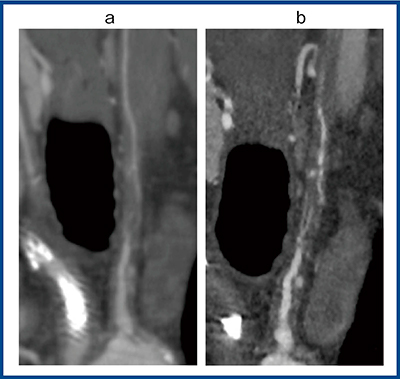

図7は左総頸動脈の高度狭窄の症例で,ADCT(a)では縦に長い血栓(→)があり,ほぼ完全閉塞しているように見えるが,Aquilion Precision(b)によるフォローアップでは,閉塞しているわけではなく,内部に細い側副血行路が発達して連続性があることが確認できた(○)。冠状断方向からの拡大画像(図8)でも,Aquilion Precision(b)では血管内部に順行性の血流が認められ,完全閉塞ではないことが診断できた。

図8 図7と同一症例の冠状断拡大画像

a:ADCT b:Aquilion Precision